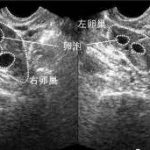

瑞丁CEF国际生殖妇产医院